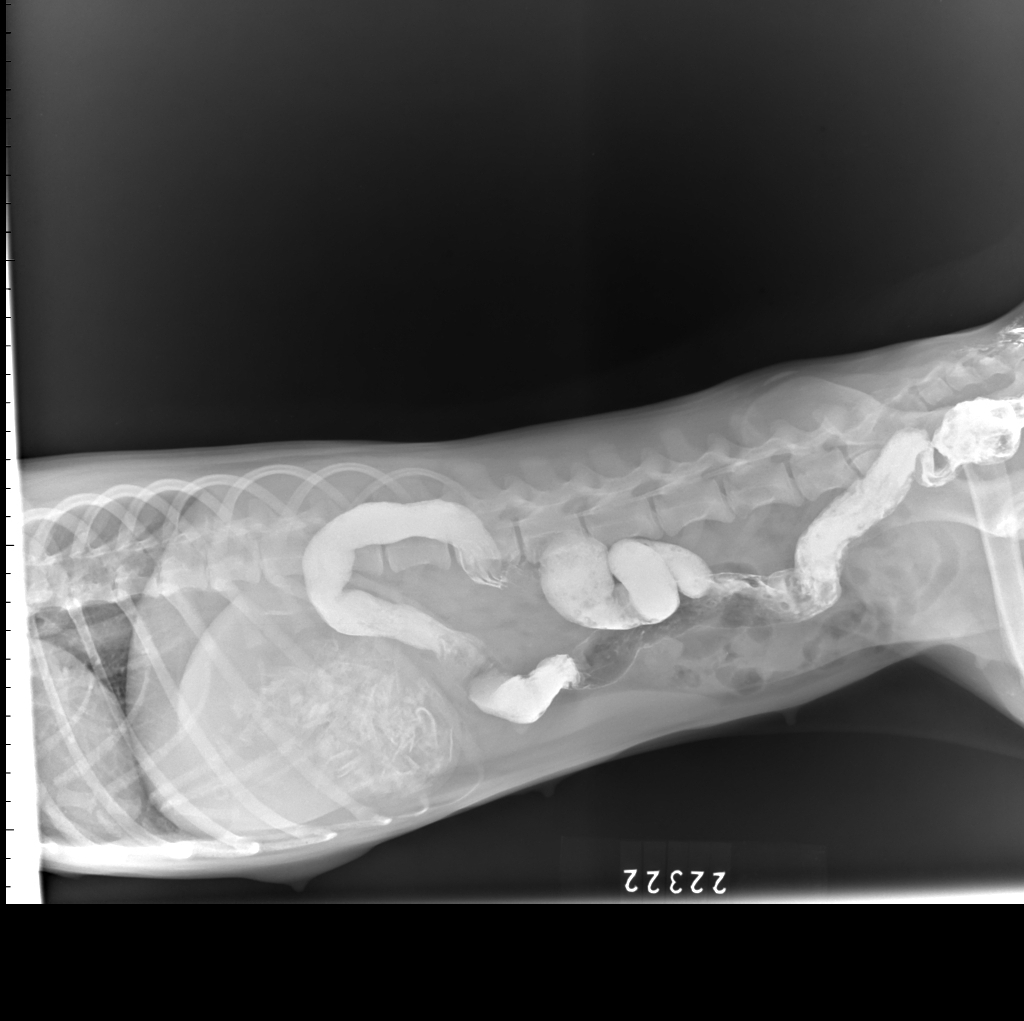

结肠灌肠造影侧位片2